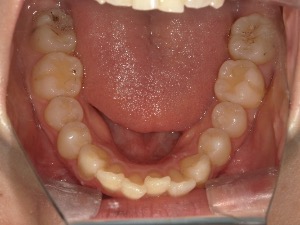

before

患者さんの年齢 20代 女性 症状 見た目が良くなりたい 治療内容 マウスピース矯正治療 費用 90万(税抜) 治療期間・回数 治療期間2年半、通院回数20回 メリット スマイルラインが綺麗 デメリット・リスク 期間がかかることがある 患者さまの声 見た目が綺麗になった - マウスピース矯正